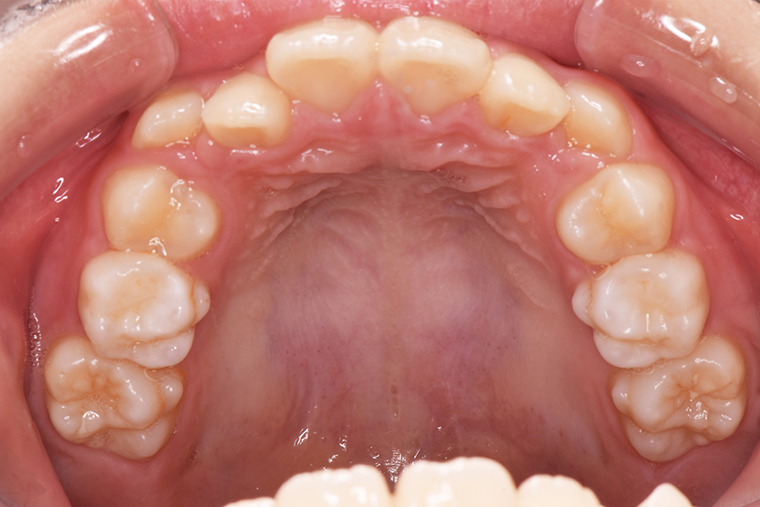

Case Study9歳女性ガタガタな歯のマウスピース矯正-矯正期間1年6ヶ月